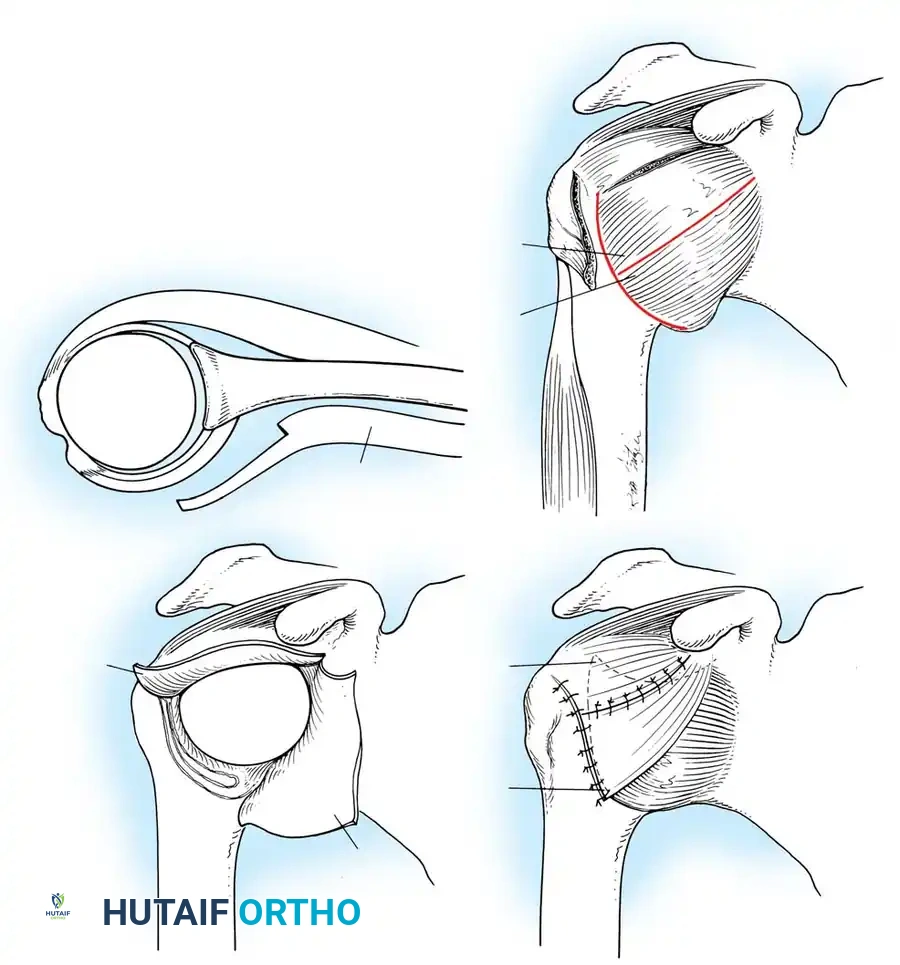

A vertical or T-shaped capsulotomy is performed based on the degree of capsular laxity and the planned shift.

- For a standard Bankart repair with an inferior capsular shift, a vertical incision is made 1 cm medial to the humeral articular margin. A horizontal limb can be added to create superior and inferior capsular flaps.

- Tagging sutures are placed in the capsular flaps for traction.

- A Fukuda retractor is placed within the joint to retract the humeral head laterally and posteriorly, exposing the anterior glenoid rim and labrum.

Capsular Shift and Closure

To address capsular redundancy, an inferior capsular shift is performed.

- The arm is positioned in 30 to 45 degrees of abduction and 20 degrees of external rotation.

- The inferior capsular flap is advanced superiorly and laterally, tensioning the IGHL complex. The sutures from the anchors are passed through the shifted capsule and tied.

- The superior flap is then brought down over the inferior flap in a "pants-over-vest" fashion to reinforce the anterior wall and close the rotator interval.

- The subscapularis split is loosely approximated with absorbable sutures. The deltopectoral interval is closed over a suction drain (if necessary), followed by routine subcutaneous and skin closure.